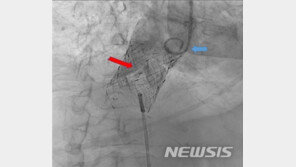

심장 판막 질환자의 가슴을 열지 않고대퇴정맥을 활용해 병든 판막을 새 인공판막으로 교체하는 시술이 국내에서 처음으로 성공했다. 가톨릭대학교 서울성모병원은 장기육 심뇌혈관병원 교수가 국내에서 처음으로 중증 삼첨판 폐쇄부전증을 앓고 있는 최모(52, 여)씨에게 수술 없이 대정맥을 이용…